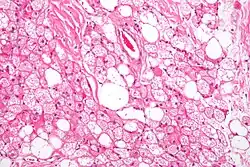

In contrast to white adipocytes, which contain a single lipid droplet, brown adipocytes contain numerous smaller droplets and a much higher number of (iron-containing) mitochondria, which gives the tissue its color.[3] Brown fat also contains more capillaries than white fat. These supply the tissue with oxygen and nutrients and distribute the produced heat throughout the body.

Brown fat in humans in the scientific and popular literature refers to two cell populations defined by both anatomical location and cellular morphology. Both share the presence of small lipid droplets and numerous iron-rich mitochondria, giving the brown appearance.

- "Classical" brown fat is found in highly vascularized deposits in somewhat consistent anatomical locations, such as between the shoulder blades, surrounding the kidneys, the neck, and supraclavicular area, and along the spinal cord. This is the smaller of the two types and has numerous small lipid droplets.

- Beige fat is the adrenergically inducible cell type that is dispersed throughout adipose tissue. It has greater variability in lipid droplet size and a greater proportion of mitochondria to lipid droplets than white fat, giving it a light brown appearance.[18] In mouse and human organoid models, EPAC1 (exchange proteins directly activated by cAMP) was reported to preferentially increase the production of beige fat relative to WAT.[19]